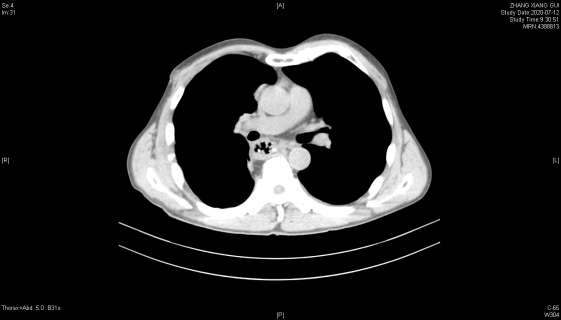

2020年7月12日 术后2周复查胸部CT

患者术后一般情况良好,术后10天逐渐恢复正常进食,进食过程通畅,无进食哽咽感等不适。